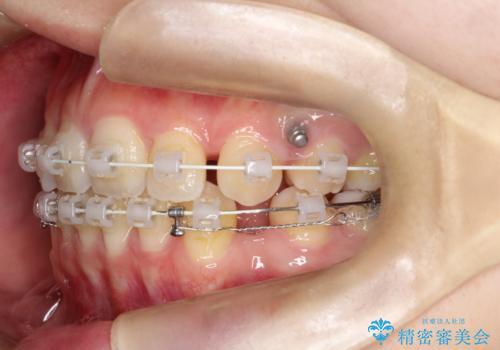

- 矯正装置

- 前歯のがたがたを主訴に来院されました。

上下の前歯が前方に傾斜しているのもあり、内側に前歯をひっこめるために上下左右の歯を1本ずつ抜歯して矯正することとしました。